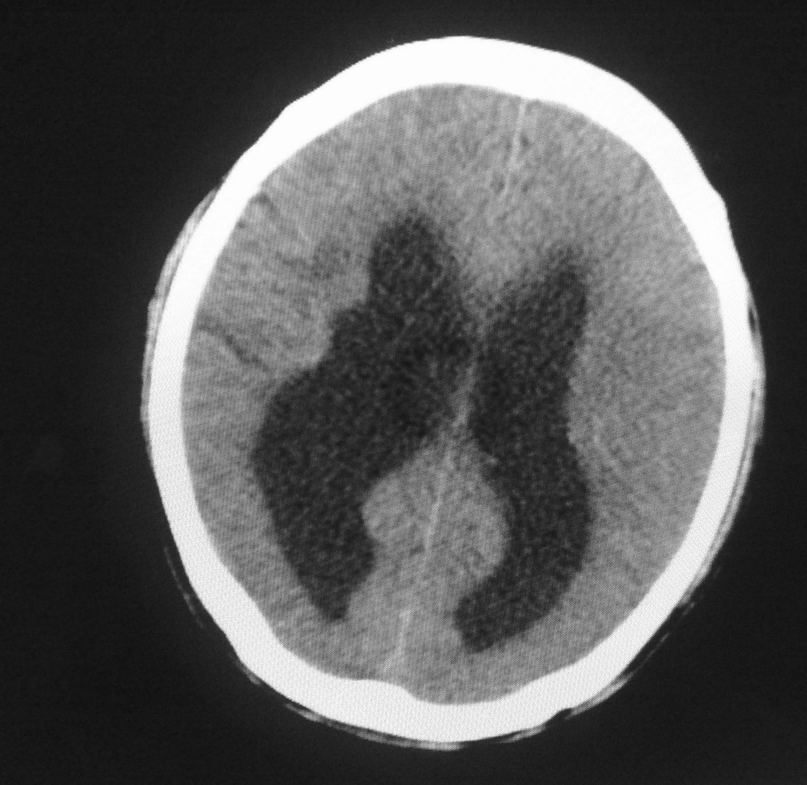

标题: CT24862:男,61岁,发热,有脑出血病史。 [打印本页]

男,61岁,发热,有脑出血病史。

右侧基底节,放射冠软化灶,胼胝体发育不良 脑积水原因待查。

脑积水【脑室血块阻塞?】

脑积水!四脑室显示不清,导水管梗阻?建议mri!

右侧基底节及放射冠软化灶,脑积水,四脑室显示不清,导水管梗阻?建议mri!

梗阻性脑积水,出血后粘连所致

1)右侧基底节区、右侧放射冠及右侧丘脑软化灶。2)脑积水。